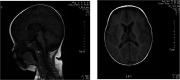

Case presentation: We reported two Chinese siblings born with a weakness in all limbs. They experienced rapidly progressive weakness in distal limbs. At the age of 6 years, the elder brother presented with severe scoliosis and cervical kyphosis. They both had global developmental delay and a CNS involvement with cognitive deficits and swallowing problems. Genetic screening in the patients' family for inherited diseases was recommended. Novel compound heterozygous variants in the FIG4 gene (c.2148delTinsAA and c.317A > G) were found by whole-exome sequencing in the patients. These variants were confirmed by Sanger sequencing in family members.

Conclusions: Herein, we reported two Chinese male patients with CMT4J who presented with abnormal CNS features. CMT4J with CNS involvement has been very rarely reported. We hoped this study could expand the phenotypic and genetic spectrum of FIG4-related diseases. And we helped physicians to understand the genotype-phenotype correlation.